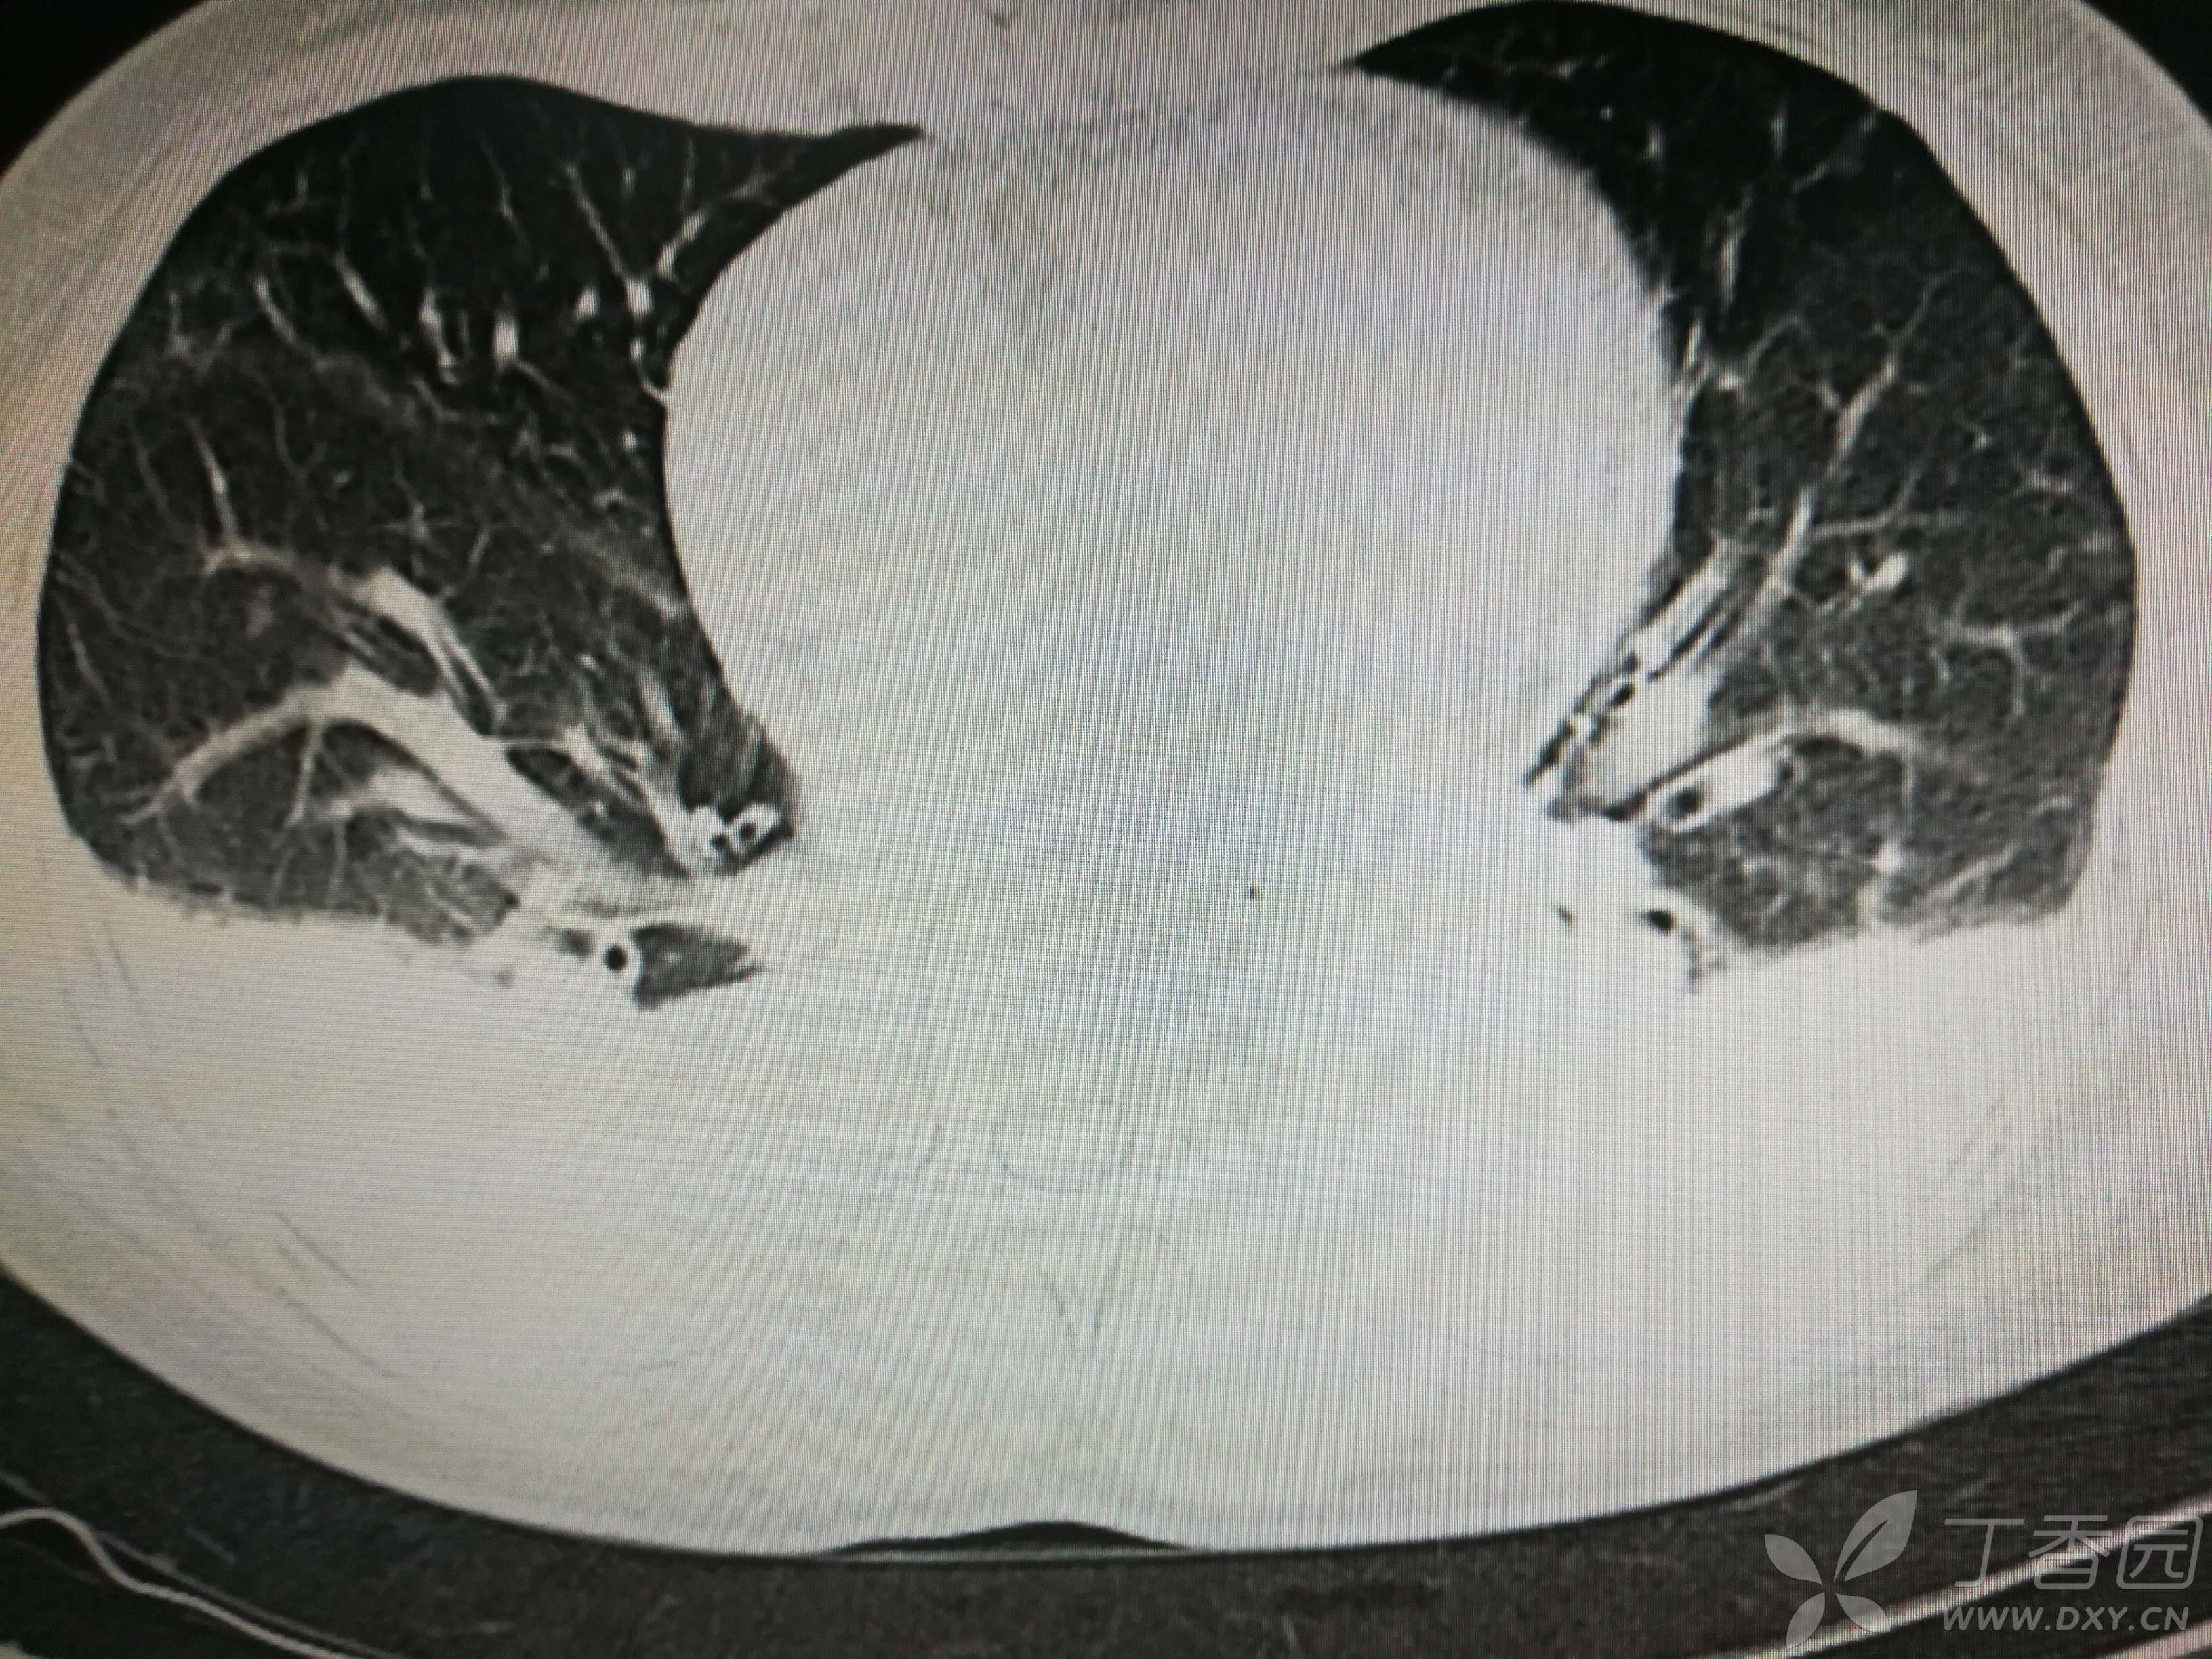

给予低分子肝素钙针抗凝、七叶皂苷钠针消肿及骨牵引固定等等治疗。入院后第四天行“左侧股骨下段骨折切开复位内固定术”(术前查双下肢彩超:双下肢深静脉血流通畅),手术顺利,术后予预防感染、预防血栓形成等治疗。术后患者无明显发热,生命体征平稳。术后第四天复查血常规:白细胞13.4×109/L,血红蛋白84g/L,血小板在正常范围。生化:白蛋白35.7g/L,余无明显异常。当天,患者开始出现轻度胸闷气急,可耐受。术后第五天患者胸闷气急加重,无胸痛,无背痛,无咯血,无意识障碍,无头晕头痛,无恶心呕吐等,急查凝血功能:纤维蛋白原降解产物12mg/L,D二聚体4000ug/L,余无明显异常。查动脉血气分析:pH7.52,氧分压62mmHg,二氧化碳分压30mmHg,碱剩余1.8mmol/L,乳酸1.0mm/L,血红蛋白86g/L。查胸部CT见下(先视频后图片):